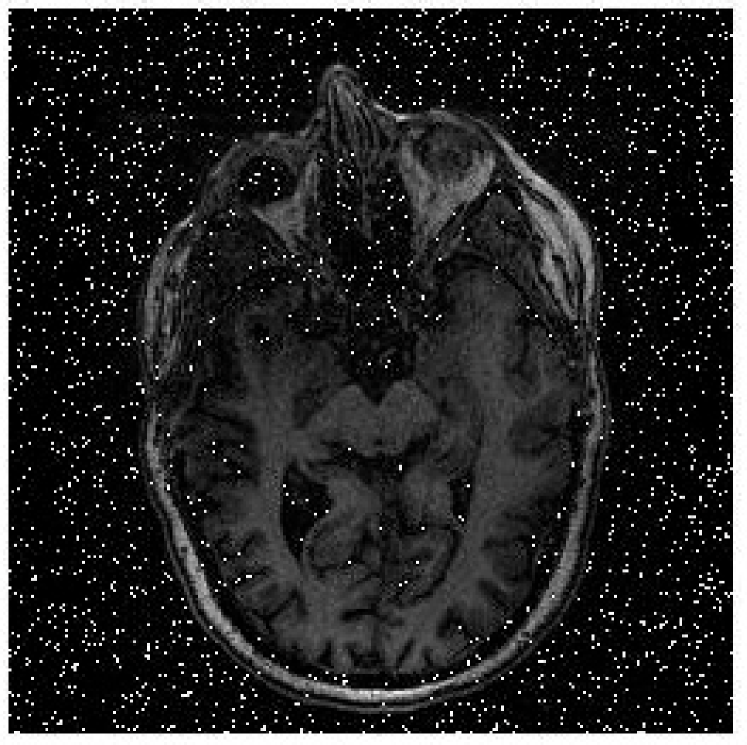

Fig.9 shows a comparison of reconstructed medical images at different signal-to-noise ratios (SNR) of 5 dB, 10 dB, and 20 dB. The results demonstrate that as the SNR increases, the quality of the reconstructed images also improves. Additionally, Fig.10 illustrates the relationship between signal-to-noise ratio (SNR) and bit error rate (BER) which is a key indicator of the performance of an OFDM system in image transmission. The figure shows that as SNR increases, the BER decreases, indicating that the OFDM system performs better in terms of image transmission quality. It also highlights the importance of having a high SNR in achieving reliable image transmission using the OFDM technique. In comparison to previous work on secure image transmission, our proposed method has demonstrated superior performance in terms of bit error rate (BER). Specifically, our method achieved a lower BER of 0.005 compared to 0.007 in SNR=30db obtained in [8]. This highlights the effectiveness of our proposed approach in improving the security and reliability of image transmission.

(a) (b)

(c)